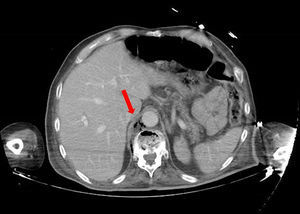

Paciente de 62 años con cuadro de astenia, febrícula y dolor lumbar de un mes de evolución, que ingresa por hipotensión arterial y oligoanuria. En la analítica destaca acidosis metabólica grave y fracaso renal agudo. Se realiza una TAC de abdomen, con presencia de múltiples burbujas aéreas localizadas en retroperitoneo superior, que parecían provenir del espacio interdiscal D10-D11, (figs. 1 y 2). La evolución posterior fue fatal, siendo exitus. El retroneumoperitoneo es un hallazgo radiológico poco frecuente, con sintomatología clínica larvada e inespecífica. La espondilodiscitis es también una infección infrecuente que afecta al cuerpo vertebral y espacios intervertebrales. Un diagnóstico precoz es fundamental para instaurar tratamiento adecuado y mejorar el pronóstico de esta enfermedad.